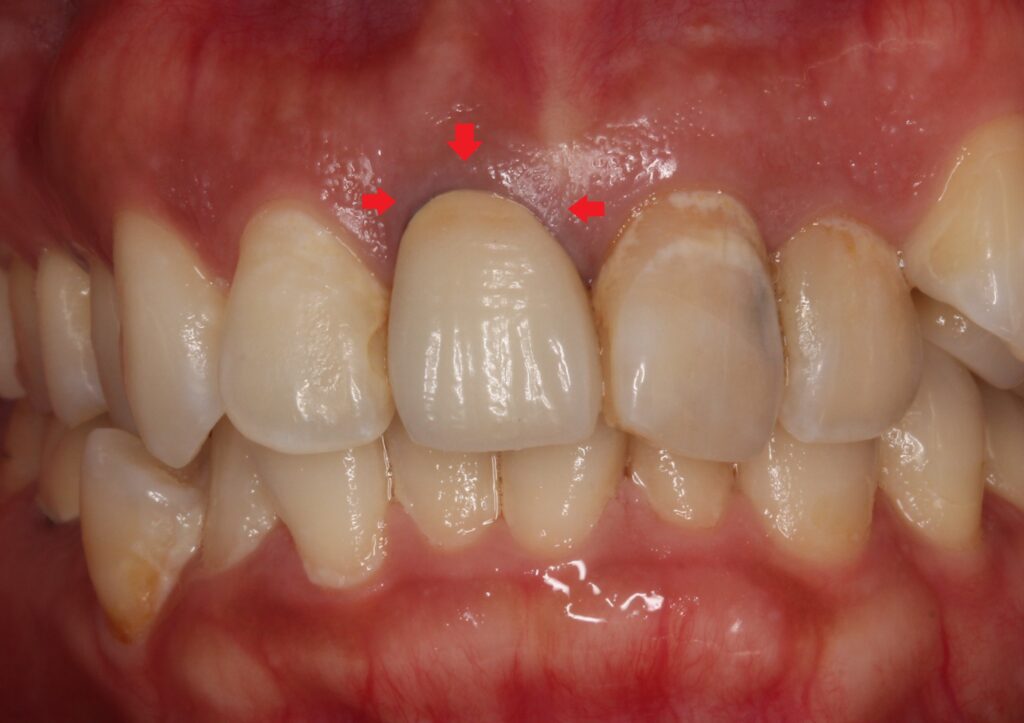

- 被せ物の歯ぐきがメタルタトゥーのように黒くなっている

金属を使った被せ物は、金属の色が歯ぐきに透けるために、

歯ぐきが黒く見えます。

これは患者さんが最初に言っていた「メタルタトゥー」とは違い、被せ物をやり直すことで改善が見込めます。

メタルタトゥーは歯ぐきに金属が入り込んでいるために、被せ物を変えるだけでは改善しません。

また青い矢印の左側の歯は、歯並びの関係でねじれて、歯の向きが変わってしまっています。